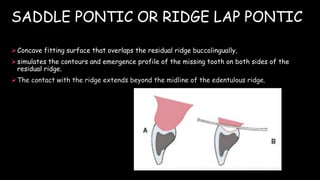

The document discusses pontic design for fixed dental prostheses. It covers pretreatment assessment of residual ridge contours, classifications of ridge deformities, surgical modification techniques, and ideal requirements for pontics. Pontic designs are classified based on their shape and materials. Factors in pontic selection include esthetics and oral hygiene. Common designs for anterior and posterior regions are described, including sanitary, ovate, and saddle pontics. Biological considerations for pontic design involve maintaining the residual ridge, abutment teeth, and supporting tissues.